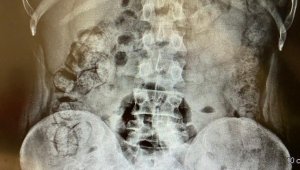

İran'dan gelen 5 kişinin midesinde 6 kilo 145 gram afyon sakızı ele geçirildi

İran'dan gelen 5 kişinin midesinde 6 kilo 145 gram afyon sakızı ele...

Uyuşturucuları yuttukları belirlendi